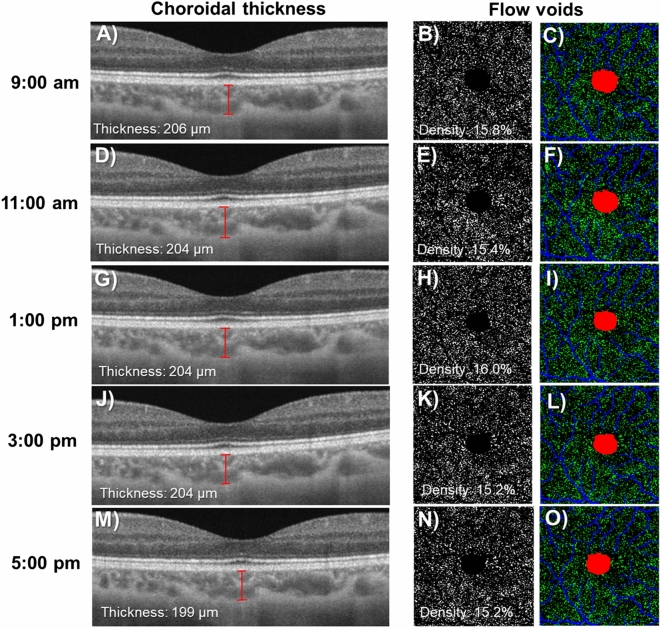

Table 1 shows the change in choriocapillaris flow voids and choroidal thickness throughout the day. The features of choriocapillaris flow voids did not change significantly over time on the first visit, where the density was 16.2 ± 1.1%, average size of flow void was 359.6 ± 26.6 µm and number was 3,579.4 ± 151.5 (P > 0.05; Table 1 and Fig. 1A–C). These findings remained similar for the second visit. In terms of choroidal thickness, there was a small but statistically significant decrease in the thickness over time (Table 1 and Fig. 1D). On average, the choroid was thickest at 9:00 am at 297.7 ± 92.1 µm, followed by 295.7 ± 91.0 µm at 11:00 am, 293.6 ± 89.5 µm at 1:00 pm, 295.7 ± 91.8 µm at 3:00 pm and thinnest 293.8 ± 91.5 µm at 5:00 pm (P < 0.005) for the first visit. These findings remained similar for the second visit (P < 0.002). Figure 2 shows an example of a patient where the thickness of the choroid was impacted by diurnal variation, while the density of the choriocapillaris flow voids remained unaffected.

Figure 2.

Choroidal thicknesses (A, D, G, J, and M) decreased throughout the day whereas the density of flow voids as seen in the binarized (B, E, H, K, and N) and color-coded (C, F, I, L, and O) images appeared consistent. Images A, D, G, J, and M were generated from the built-in review software (PLEX Elite Review Software, Carl Zeiss Meditec, Inc., Dublin, USA; Version 1.7.1.31492; https://www.zeiss.fr/content/dam/Meditec/international/ifu/documents/plex-elite/current/2660021169042_rev._a_artwork.pdf).